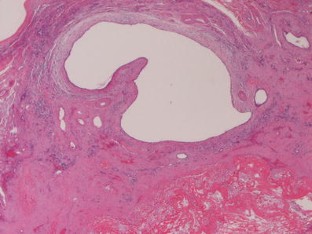

We herein report a case of monolobar hepatobiliary fibropolycystic disease. A 75-year-old woman presented with heartburn. Imaging modalities including US, CT, and MRI revealed marked atrophy and multiple biliary cysts of the hepatic left lobe. The hepatic right lobe was normal. ERCP and bile duct endoscopy revealed anomalous pancreaticobiliary union, choledochal dilation, dilation of left intrahepatic bile ducts, and small choledochal non-invasive adenocarcinoma. Polycystic kidney diseases were absent. The patient underwent pancreatico-duodenectomy and extended hepatic left lobectomy. Grossly, the hepatic left lobe was markedly atrophic, and studded with numerous biliary cysts. The left intrahepatic bile ducts were dilated (Caroli’s disease) and the common bile duct showed type I choledochal dilation. The right hepatic lobe was normal. Histologically, the hepatic left lobe was replaced by fibroelastosis. The intrahepatic bile ducts showed ductal plate malformation such as irregular contours, invaginations, and protrusions. The numerous biliary cysts also showed ductal plate malformation. There were numerous persistent ductal plates and microhamartomas. Many hyalinized destructive biliary cysts and ductal plates were recognized. The liver parenchyma was scant and free of hepatocellular malformations. The portal veins showed old obliterative portal thrombosis. The right hepatic lobe was normal. Immunohistochemically, the biliary cells were positive for cytokeratin 7, 8, 18 and 19, and MUC6 and CD10, but negative for MUC2 and MUC5AC. The biliary cysts, persistent ductal plate, and microhamartomas were positive for fetal apomucin antigen MUC1.

Fig. 1